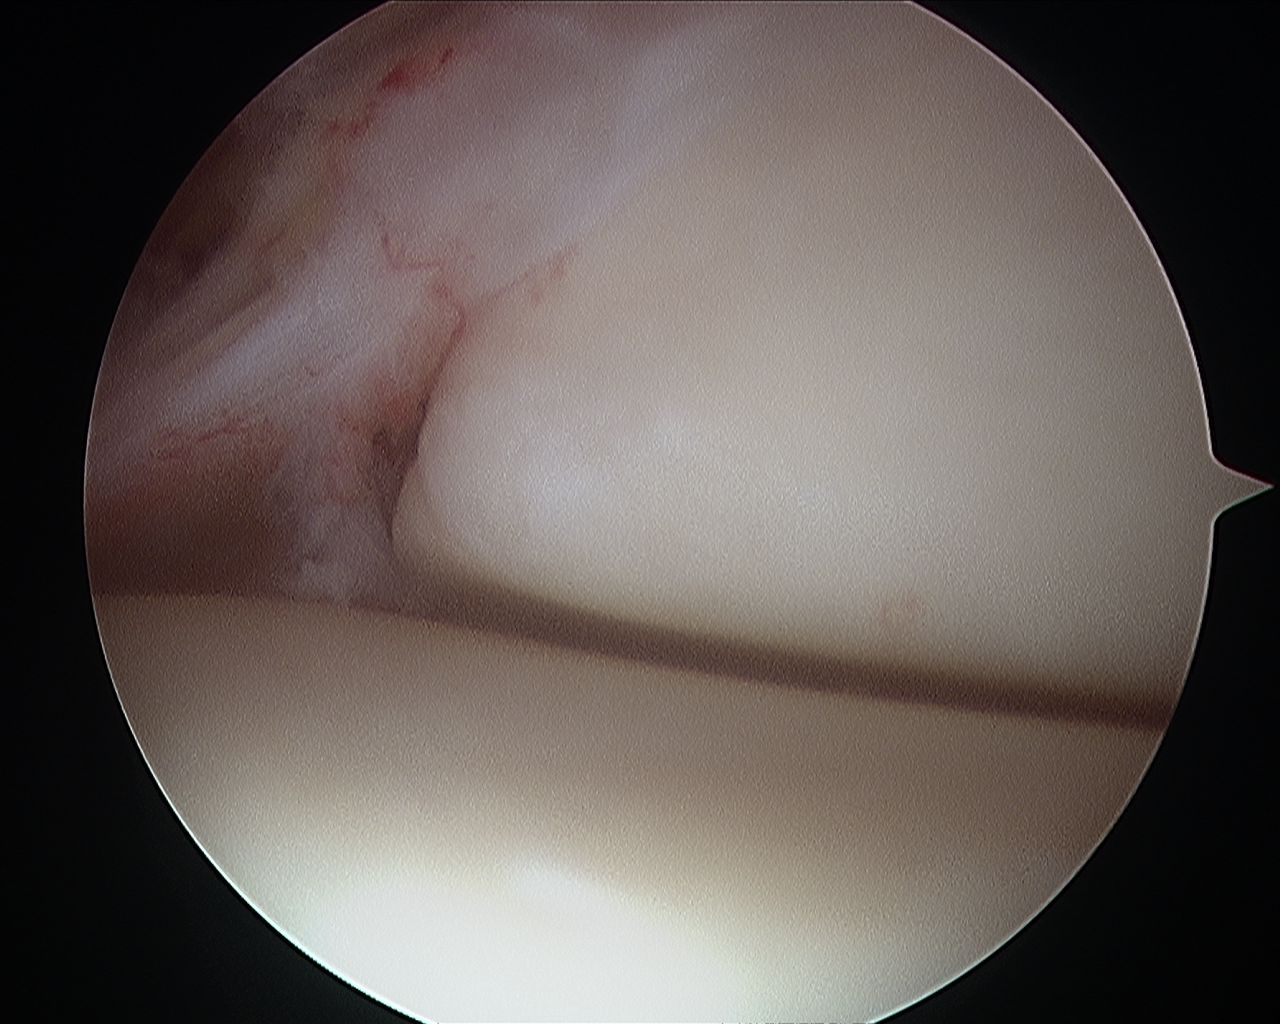

Αρθροσκοπική Αντιμετώπιση Παθήσεων Μηνίσκου